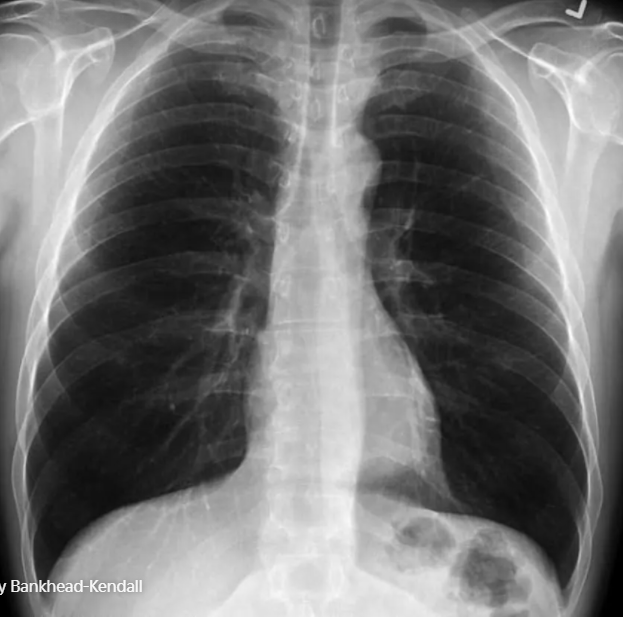

Theo thứ tự, ảnh đầu tiên là phổi của người khỏe mạnh bình thường, ảnh thứ 2 là phổi của người hút thuốc và cuối cùng là phổi của bệnh nhân Covid-19. Có thể thấy lá phổi trong ảnh đầu tiên sẫm màu và không có vết tích lạ, ảnh thứ 2 có sẹo, còn phổi trong ảnh thứ 3 lại mờ đục vì chất nhầy.

Lá phổi của người khỏe mạnh.